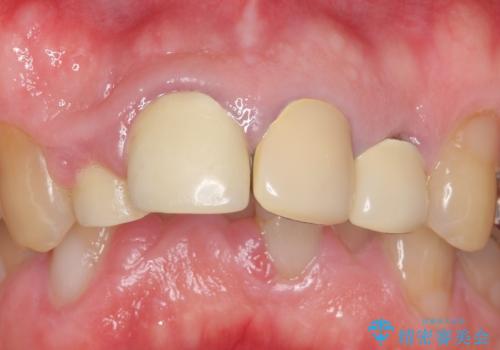

再根管治療後、オールセラミッククラウンによる補綴を行いました。

右上2は歯茎のラインを整えるため歯周外科を行っております。

今回用いたオールセラミッククラウンは、ジルコニアフレームという白い素材の上にセラミックを盛っているため審美性が非常に高いのが特徴です。

またジルコニアは人工ダイヤモンドの材料にも使われているほど高い強度を持っており、そのためオールセラミッククラウンは審美性だけでなく、奥歯やブリッジの補綴も可能とするクラウンです。